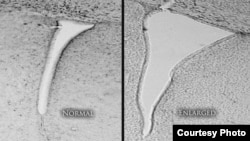

When they examined the brains of the pollution-breathing mice, they found the lateral ventricles – part of the brain’s cerebrospinal fluid circulatory system – were two to three times the normal size.

In humans, this enlargement is associated with autism, schizophrenia and more, Cory-Slechta said. “It is an indicator of poor development. It is a prognosis for poor development of children with behavioral, IQ, cognitive, and other kinds of deficits that will persist.”

When they examined the brains of the pollution-breathing mice, they found the lateral ventricles – part of the brain’s cerebrospinal fluid circulatory system – were two to three times the normal size.

In humans, this enlargement is associated with autism, schizophrenia and more, Cory-Slechta said. “It is an indicator of poor development. It is a prognosis for poor development of children with behavioral, IQ, cognitive, and other kinds of deficits that will persist.”